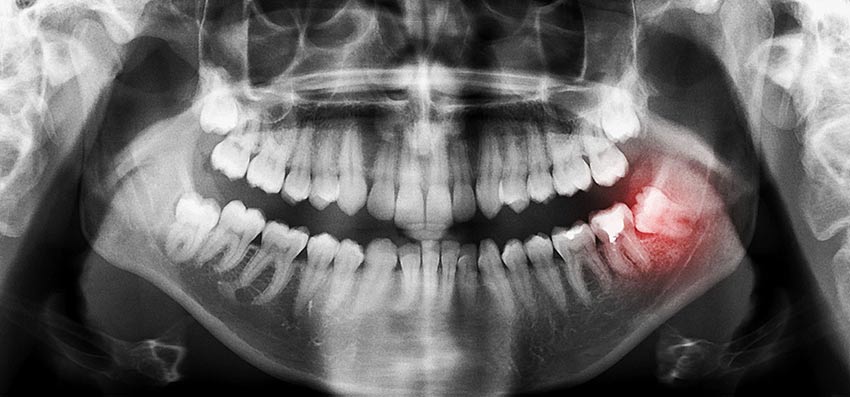

Studije pokazuju da učestalost impakcije umnjaka varira od 17% do 32%. Međutim, važno je napomenuti da svi impaktirani umnjaci neće nužno stvoriti probleme pacijentima. Iako mnogi ljudi nemaju simptome, simptomi na koje treba reagovati uključuju pojavu bola, otoka i crvenila u regiji neizniklog zuba, kao i otežano otvaranje usta.

Redovni stomatološki pregledi i RTG dijagnostika omogućavaju pravovremeno utvrđivanje prisustva impaktiranih umnjaka i prevenciju mogućih problema.

Sam proces vađenja umnjaka počinje pregledom i rendgenskim snimkom, kako bi se tačno odredio položaj zuba i korijenova. Zatim se daje lokalna anestezija, pa kada regija potpuno utrne, stomatolog specijalnim instrumentima olabavi zub i izvadi ga iz ležišta, a kod impaktiranih umnjaka po potrebi pravi mali rez na desnima i uklanja dio okolne kosti. Na kraju se rana ispere, eventualno ušije, postavi se tampon i dobijate uputstva kako da se ponašate narednih sati i dana.